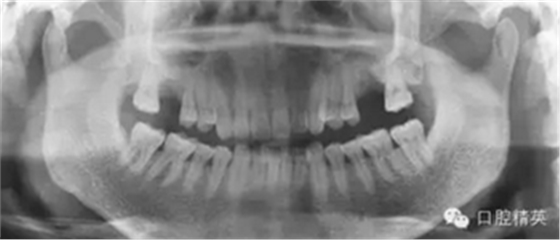

3个月后来进行种植手术,颌骨曲面断层片

检查口腔种植区骨和粘膜厚度为7.5MM。龈颜色正常,无瘘道。种植区牙槽骨密度接近正常,窦嵴距10MM,左上颌窦无明显炎症影像。排除曲断这个位置的20%放大率,拟做上颌窦内提升后种植ITI的10MM的种植体。